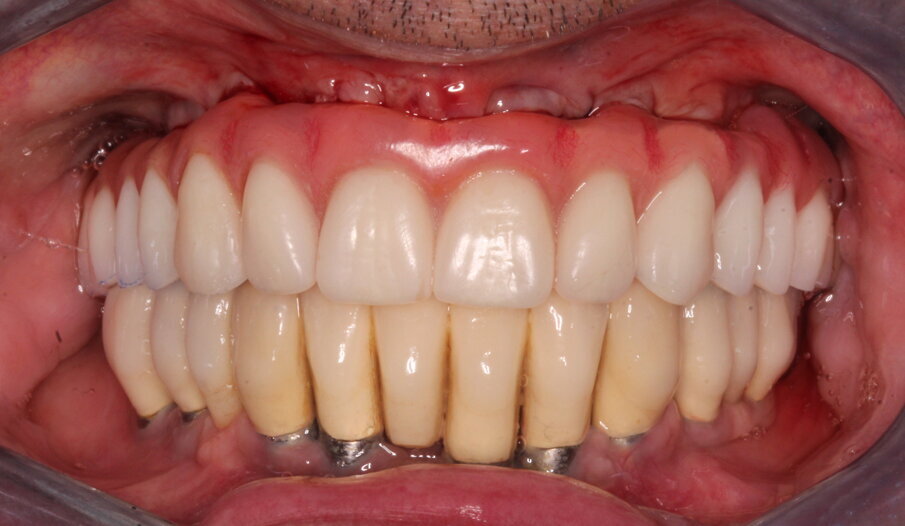

Il giorno dopo il tecnico confeziona una protesi definitiva tipo Toronto Bridge con rinforzo in Peek o altro tecnopolimero di resina termoindurente rinforzata (Trilor Arch) immerso all’interno della resina, rispettando l’aspetto estetico definito in precedenza e l’altezza verticale. Nella sua parte inferiore, la protesi presenta delle concavità in corrispondenza degli impianti e dei monconi che appaiono leggermente più grandi del diametro e dell’altezza delle cappette. Una volta verificato in bocca che la protesi sia passiva e che le cappette non frizionino alcuna parete dei fori, si termina il lavoro colmando con della resina composita Combo-Lign (bredent) lo spazio tra la cappetta e la protesi scavata precedentemente dal tecnico facendo articolare l’arcata in corso di trattamento con l’antagonista mediante una chiave articolare in silicone rigido.

La resina alla stato ancora tenero va indurita con la lampada polimerizzante per alcuni minuti; una volta controllata la masticazione anche senza la chiave articolare e fatti gli opportuni minimi ritocchi, la protesi va rimossa e rifinita a dovere, poi riaccoppiata. Una OPT di conferma serve per verificare il corretto alloggiamento delle cappette sui monconi e la passività del manufatto.

Per il paziente non ci sono fori antiestetici, in tempi rapidissimi si ottiene il definitivo (in mezza giornata) senza passare attraverso il provvisorio, si sfrutta il carico immediato anche in condizione post-estrattiva; durante le sedute di igiene orale la rimozione è facilitata ogni qualvolta lo si desideri e la seduta alla poltrona è rapidissima. Altri vantaggi prevedono l’utilizzo di poche componenti protesiche, abbassa quindi notevolmente i costi di esecuzione, con il vantaggio che il reintervento per fallimento implantare si può eseguire senza compromettere la protesi, come pure l’aggiunta di un impianto e collegarlo alla protesi può essere fatto senza problemi.

La protesi Toronto Bridge eseguita con tecnica CLIKSS presenta, rispetto alle protesi Toronto convenzionali, i seguenti vantaggi:

- non ci sono buchi antiestetici;

- non essendoci accesso a viti il materiale protesico è integro, più pulibile, meno soggetto all’infiltrazione batterica;